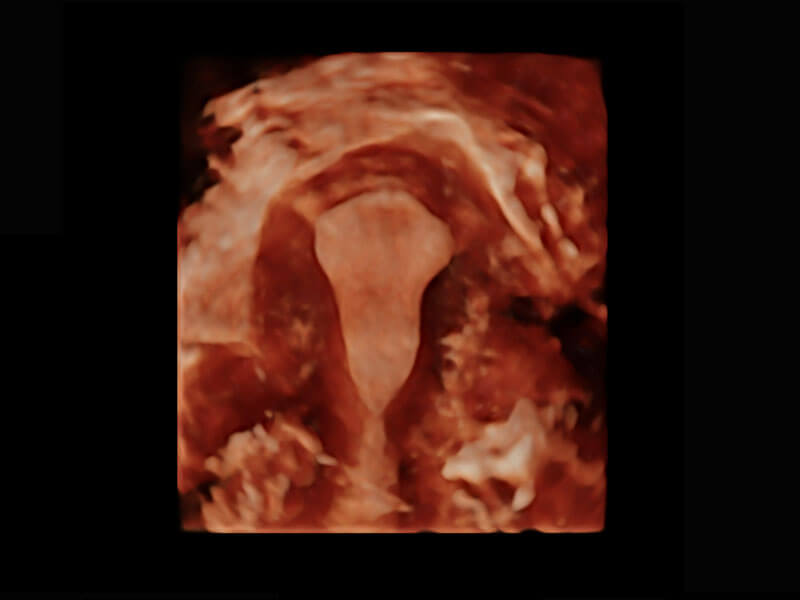

盆底超声

P60为盆底超声检查提供应用方案,多种腔内及腹部容积探头提供从二维、三维到四维的优异图像品质,实时快速三维容积数据获取,专业的测量工具包等人性化设计,为超声医生诊断提供有力保障。